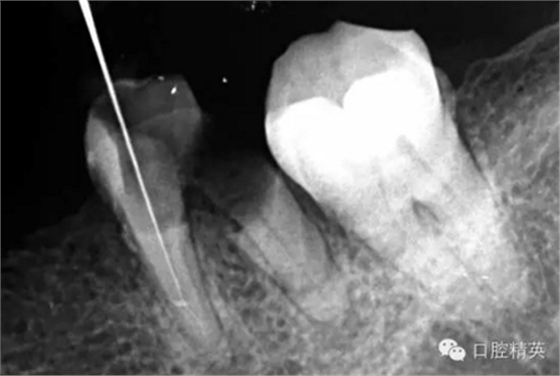

這個(gè)病例難以疏通在于根中上段堵塞,根尖下段有臺(tái)階的形成,感覺不到彎曲的方向。首先我們處理根上段,我們可以采取的方法是先預(yù)備跟中上段,將它擴(kuò)開來(lái),這樣有利于根尖下段的預(yù)備,建立良好的視野。對(duì)于根尖下段的臺(tái)階和彎曲 ,8號(hào)挫預(yù)彎,第二步要知道根管彎曲的方向,沿著根管彎曲的方向疏通。特別是有臺(tái)階的地方,一定不要硬來(lái),慢慢旋轉(zhuǎn)找到根管彎曲的方向(結(jié)合x線片)避開臺(tái)階,一定要記住慢慢旋轉(zhuǎn)角度越小越好,正旋逆旋找“緊點(diǎn)”,有經(jīng)驗(yàn)的醫(yī)生大概都知道,找到了“緊點(diǎn)”就等于找到了希望。手法一定要輕柔不易暴力!切記切記!戒浮戒躁(這句話也是特別要告訴我自己)。

近頰為疏通。慢慢找點(diǎn)可下,近頰花費(fèi)一小時(shí)。